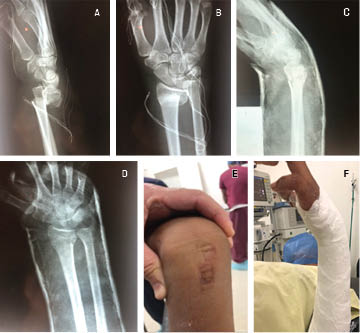

Clinical radiological evaluation of the use of a new device for the closed reduction of distal radio fractures

Distal radius fractures are frequent and represent 55% of the total in children and adults as well as 1.5% of the total emergency room visits. In children, 90% are managed with closed reduction and application of plaster; in adults, treatment varies according to type, experience of the doctor and general condition of the patient. In this setting, it is common for primary care to be delayed due to empirical events, causing significant inflammation and edema, which makes the closed reduction of the fracture difficult, causing the need for open reduction. The present work shows a steel device, designed for the closed reduction of distal radius fractures that was used in public hospitals in Navojoa, Sonora, Mexico. Thirty patients with displaced distal radius fracture with an evolution between one and seven days, from 2017 to 2019, were documented. Standard radiological measurements were performed before and after reduction, obtaining results of 96.66% of the cases with satisfactory alignment, and statistically significant difference between pre and post indices (p < 0.05). One case required surgical treatment for poor correction, no distal neurovascular complications caused by the reduction mechanism were documented. Biomechanical tests were performed on the device that showed advantages over the traditional thumb reduction technique. It is concluded that this device for the closed reduction of distal radius fractures is an effective tool and that it is possible to favor its use.

Figure 1